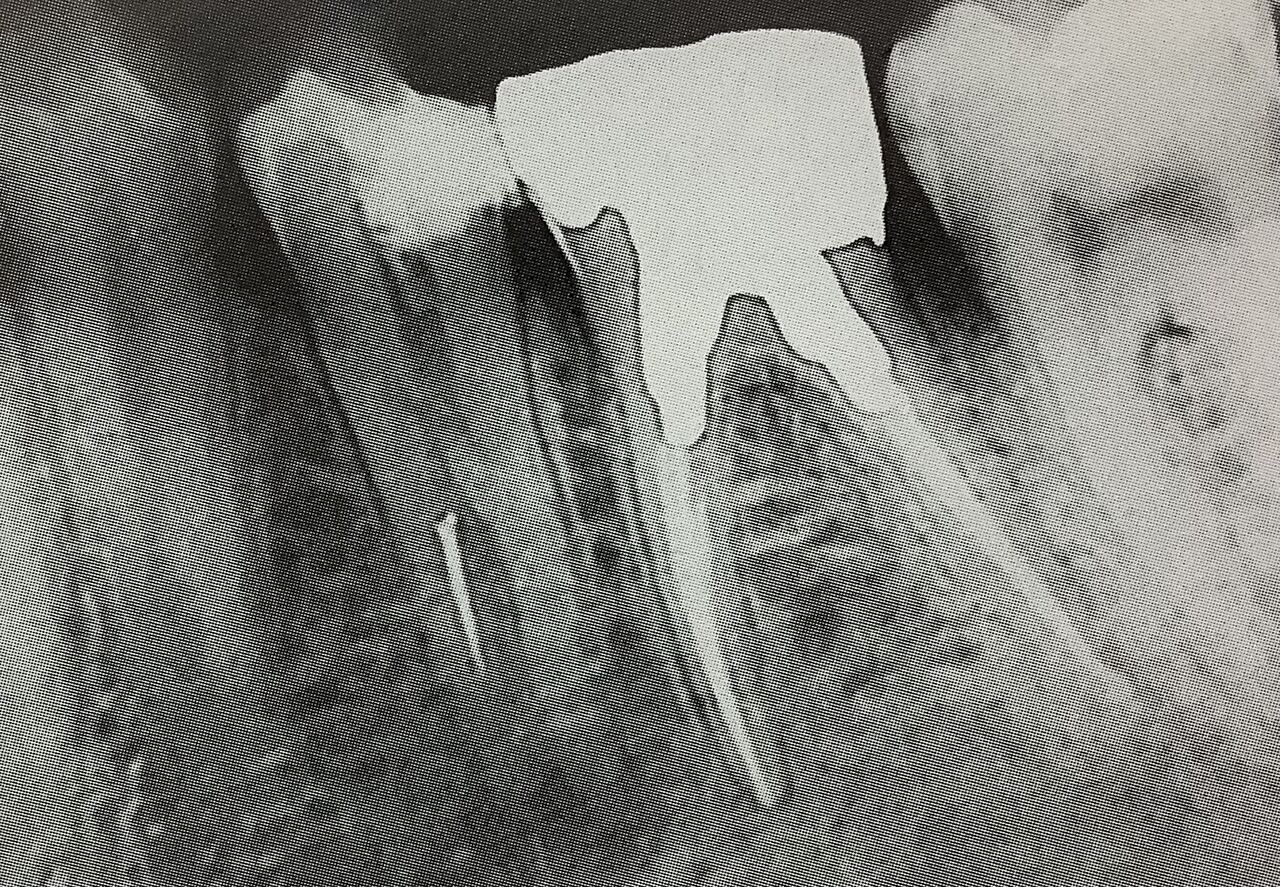

この歯は特に難しいですね。

細い根っこで途中から複数本に枝分かれしています。

中で白く見えるのが、折れちゃった器具です。

う〜ん、これまた難しいですね。